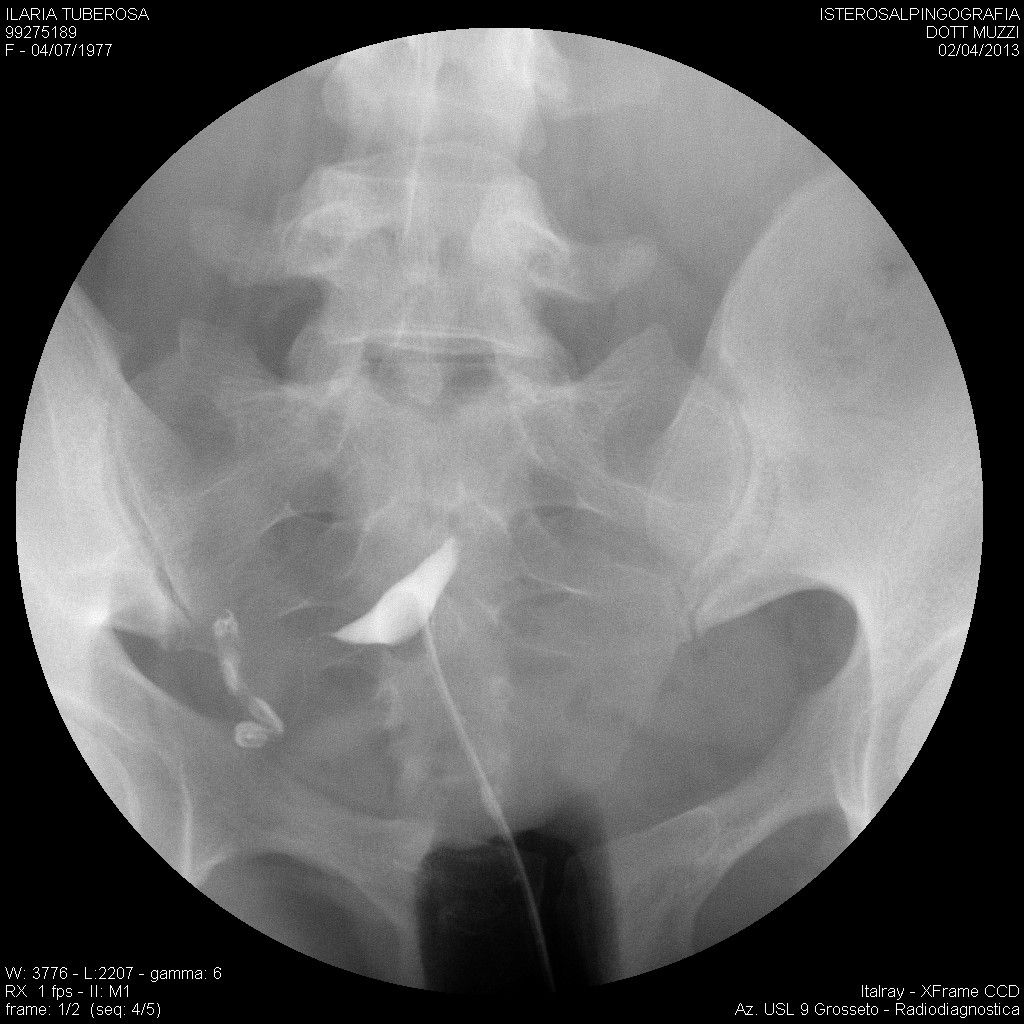

mi ritrovo a mettere in discussione un isterosalpingografia del 2013, dopo che per caso un medico radiologo la scorsa settimana ha guardato l'esame e mi ha detto che sembrerebbe pervia la tuba destra, al contrario di quanto recita il referto.

Vi allego immagini estrapolate dal cd nella speranza possiate aiutarmi nella lettura.

im000003.jpg

[ 172.85 KiB | Osservato 507 volte ]